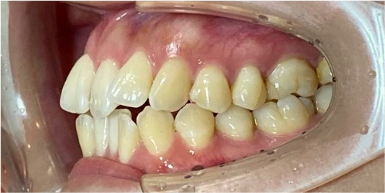

30歳女性のビフォーアフター

| 診断 | 叢生 |

| 治療方針 | 治療方針:インビザラインシステムにて主にIPR(歯と歯の間をわずかに削合してスペースを獲得する方法)を組み込んだ動的矯正治療を行い、叢生を改善後、保定を行う。 |

| 治療費 ※ | 96万5千円(診断、型取り、矯正中のメンテナンス、保定装置を含む料金) |

| 治療期間 | 1年8か月 |

| リスク | 1日20時間以上マウスピースを使用できない場合、歯が動かなかったり、想定しない誤差により不完全に終わる可能性がある。装着時や食事時に痛みを伴う。歯肉退縮や虫歯になるおそれがある。また、指導通りに装着できていない場合や適切なブラッシングが出来ていないとそのリスクが高くなる。歯根が短くなることがある。ごくまれに歯の神経が損傷してしまうことがある。過去にぶつけたり深い虫歯治療をしたことがあるとそのリスクはやや高くなる。矯正後には保定装置が必要。適切な使用ができない場合、後戻りの原因となる。将来的に歯並びが動いて再矯正が必要な場合がある。舌癖(舌で歯を押し出す癖)親知らずが正常に生えていない場合、その可能性がやや高くなる。 |